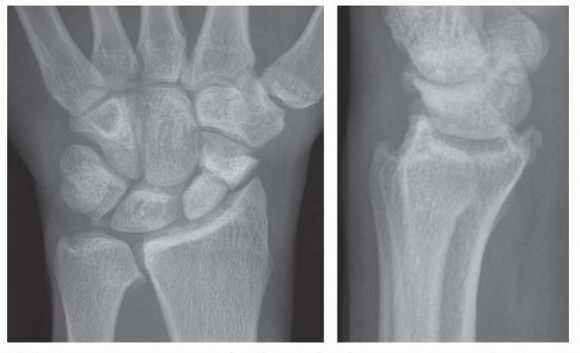

The decision to proceed with a radial styloidectomy hinges on precise clinical and radiographic staging of the radiocarpal joint. The primary, standalone indication is highly localized, symptomatic arthrosis confined strictly to the articulation between the radial styloid and the scaphoid. This is classically observed in SLAC Stage I and SNAC Stage I wrists. In these highly selected scenarios, excising the impinging styloid removes the mechanical block to motion and the source of focal synovitis. Patients typically present with point tenderness directly over the anatomic snuffbox, exacerbated by forced radial deviation and wrist extension—a maneuver that directly compresses the scaphoid against the styloid.

Pre-Operative Planning, Templating, and Patient Positioning

Meticulous pre-operative planning begins with high-quality, standardized radiographic imaging. A zero-rotation posteroanterior (PA) view, a true lateral view, and specific scaphoid views are mandatory to assess the extent of joint space narrowing, subchondral sclerosis, and osteophyte formation. The PA radiograph is critically evaluated for any evidence of ulnar variance or pre-existing ulnar translation of the carpus by assessing the radiolunate angle and the Gilula lines. Advanced imaging, specifically a high-resolution non-contrast CT scan, is highly recommended. CT provides a three-dimensional map of the arthrosis, allowing the surgeon to precisely delineate whether the degenerative changes are truly confined to the styloid tip or if they extend deeper into the scaphoid fossa.